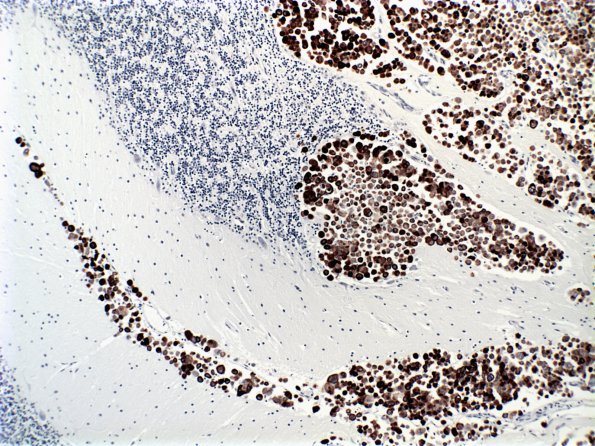

Washington University Experience | NEOPLASMS (METASTASES) | Meningeal | 6B3 Metastatic CA CK7 (Case 6)

CK7 immunohistochemistry demonstrates leptomeningeal and parenchymal metastases. The microscopic appearance of the cerebellum is remarkable for multifocal leptomeningeal carcinomatosis with an extension into the underlying cerebellar parenchyma. The tumor is characterized by generally discohesive cells with abundant eosinophilic cytoplasm and oval to markedly irregular shape hyperchromatic nuclei, sometimes with prominent nucleoli.